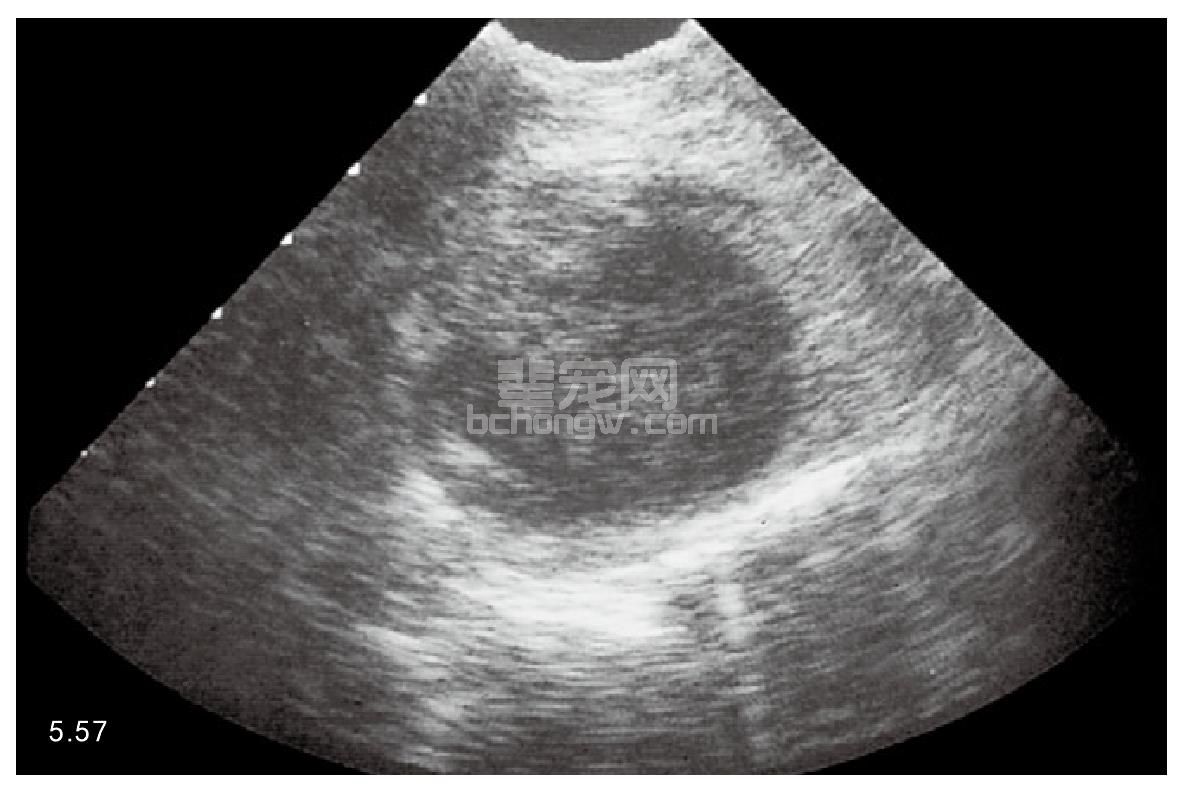

诊断 典型的病史和临床症状可以确定为前列腺疾病,外周中性粒细胞通常会出现核左移。超声检查前列 腺显示单个的或者多发的充满液体的囊状物(图5.57)。通过细针抽吸的前列腺液的细胞学检查显示有脓性分泌 物。前列腺液培养会生长出需氧菌,但是厌氧菌也可能出现。

图5.57 超声检查犬前列腺脓肿。